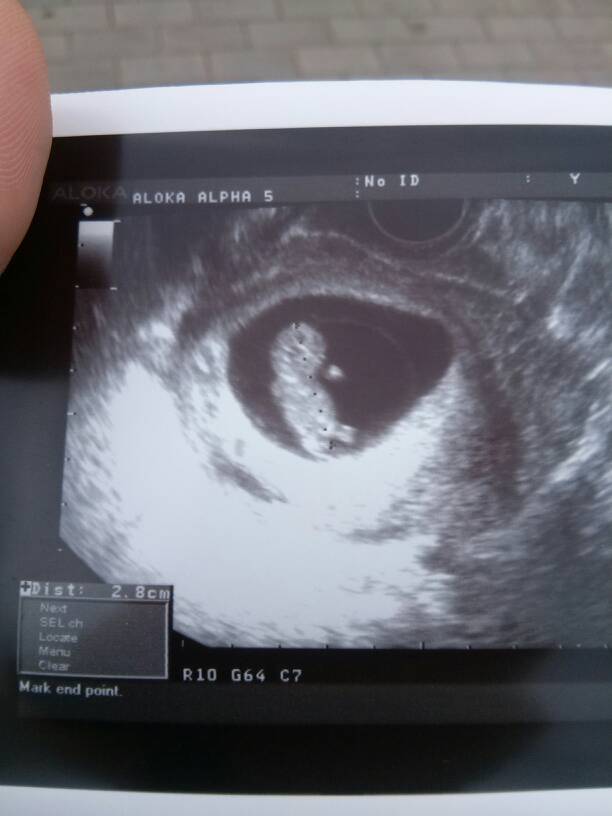

U mnie dzisiaj 10 t 1 d i wedlug USG dzidzia miala 2.8 cm, tez sie pokazemy:-)

Kathana ale duzy bobas juz:-) najwazniejsze, ze zdrowo rosnie.

----Truskaweczka--- gratki wizyty:-) to nasze maluszki do siebie podobne